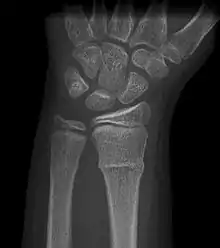

A radiograph image of a torus (buckle) fracture

A Torus fracture, also known as a buckle fracture is the most common fracture in children.[1] It is a common occurrence following a fall, as the wrist absorbs most of the impact and compresses the bony cortex on one side and remains intact on the other, creating a bulging effect.[2] As the bulge is only on one side of the bone, this injury can be classified as an incomplete fracture. The compressive force is provided by the trabeculae and is longitudinal to the axis of the long bone, meaning that the fracture itself is orthogonal to that axis.[3] The word "torus" originates from the Latin word "protuberance."[4]

Buckle fracturs can be identified by performing a radiograph. The diagnosis of a torus fracture is made from both anterior/posterior and lateral projections. The typical features include:

• The buckling of cortical bone, which may appear as a small bulge or protuberance in the radius or ulna.

• The bone may have a slight angulation.[8]